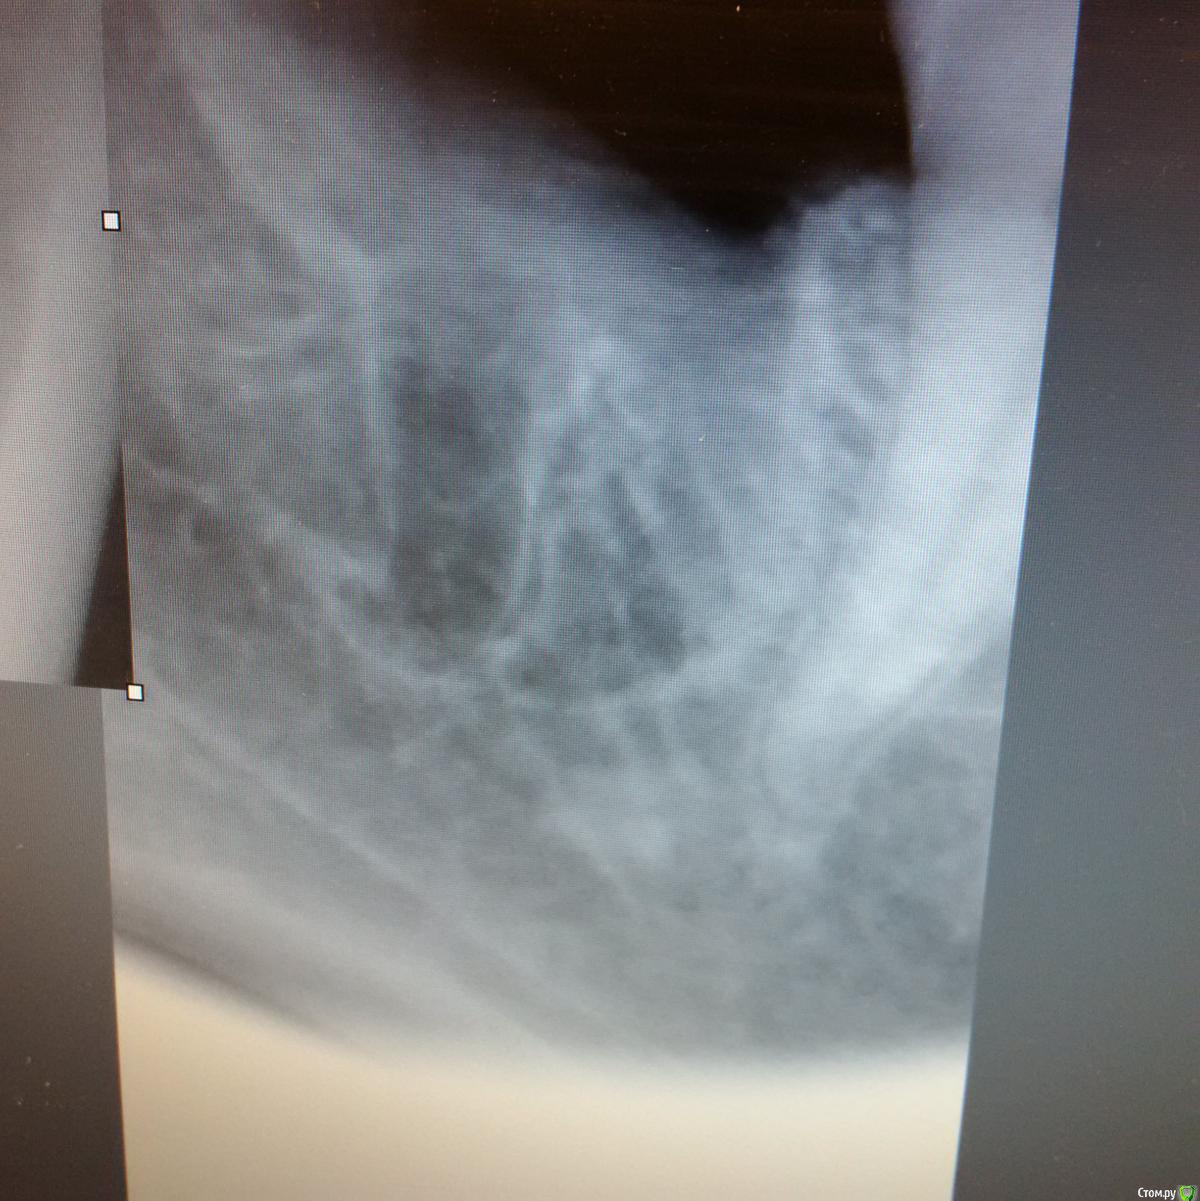

St_Klaus Опубликовано 1 апреля, 2015 Поделиться Опубликовано 1 апреля, 2015 (изменено) http://s019.radikal.ru/i644/1504/4b/175f70ea0edd.jpghttp://s017.radikal.ru/i440/1504/4b/c00d166469ac.jpghttp://s018.radikal.ru/i500/1504/19/2d8060f27545.jpghttp://s011.radikal.ru/i315/1504/33/ef8c5b099365.jpghttp://s018.radikal.ru/i513/1504/54/6aef06292c7b.jpg Изменено 1 апреля, 2015 пользователем St_Klaus 6 Ссылка на комментарий

kOIIImaRik Опубликовано 1 апреля, 2015 Поделиться Опубликовано 1 апреля, 2015 (изменено) Восьмерочка, верхняя. апексы худенькие-худенькие. Повезло Изменено 1 апреля, 2015 пользователем kOIIImaRik 3 Ссылка на комментарий